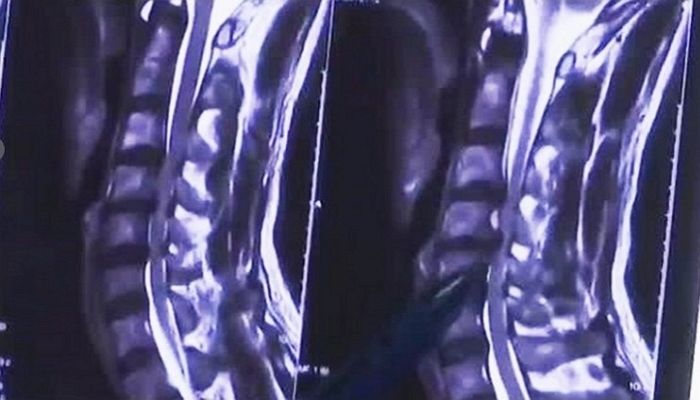

医師による検査結果は、「悪い姿勢であまりにも長い時間座って、脊椎に無理が来たようだ」、「脊髄損傷が呼吸困難につながった」と伝えてくれました。

続いて、「もう少し遅かったら、椎間板ヘルニアはもちろん、全身麻痺する障害になるところだった」、「同じ姿勢でずっと、スマホを継続的に見るのは非常に危険だ」とアドバイスしました。